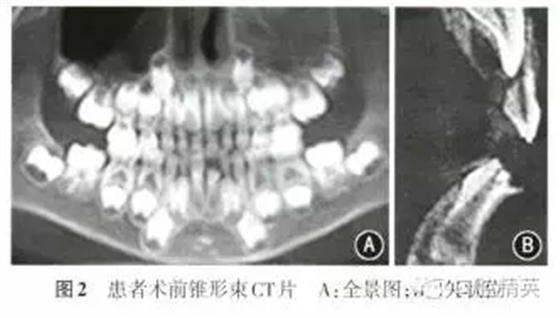

患者男性,7歲10個月,因左下乳前牙脫落后長出一牙尖半年余要求治療,于2014年11月至南昌大學(xué)附屬口腔醫(yī)院口腔頜面外科門診就診?;颊呒韧w健,無牙病及外傷史,無家族史。體格檢查示身體發(fā)育正常,口腔檢查:II缺失,l缺牙區(qū)唇側(cè)可見一圓錐形牙尖突出于牙齦表面,色澤正常(圖1);66616已萌出,混合牙列,余未見明顯異常。錐形束CT檢查示1唇側(cè)鷹爪狀畸形尖,直徑約1.0 mm,長度約3.2 mm,尖端離切緣約2.6 mm,不與髓腔相通;切緣形態(tài)亦發(fā)育異常,近髓角;牙根發(fā)育至根長1/2左右,根尖呈喇叭狀;無先天性牙缺失及額外牙(圖2)。